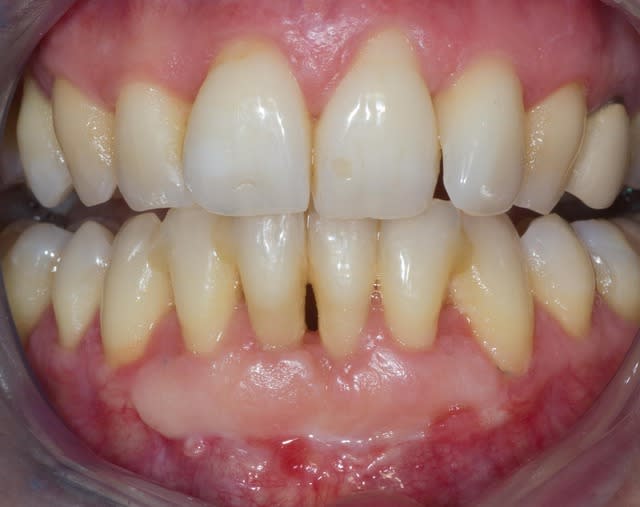

Comme on voit pas bcp de muco sur eugenol

P'tite 23 qui montrait trop de racine

Les 2 dernières photos sont à la dépose des fils (14 jours)